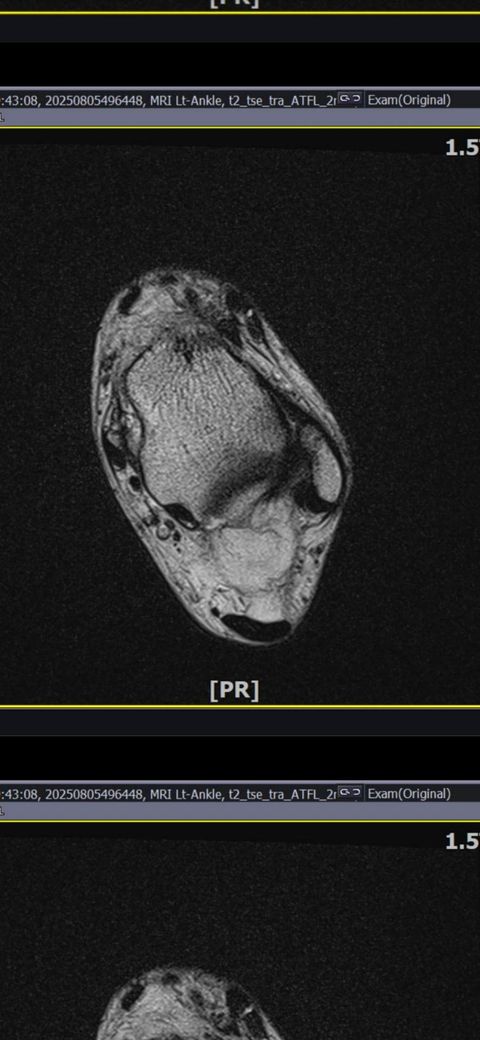

발목인대 상태 질문드립니다. (mri사진 첨부)

그런데 다친 지 2주 뒤부터 발목이 쑤시듯 아파 병원에서 초음파 검사를 했고, 전거비인대(ATFL) 2도 염좌 진단을 받았습니다. 이후 약 6주 동안 주 1회씩 충격파, 물리치료, 도수치료 등을 받았습니다. (고정치료는 시기가 늦었다며 진행하지 않았습니다.)

그래도 통증이 남아 8월 5일에 MRI를 촬영했는데, 병원에서는 “인대는 이어져 있고, 이 정도면 재활운동으로 호전될 것”이라는 설명을 들었습니다.

MRI 상 전거비인대와 발목 상태가 정말 회복 단계인지, 아니면 만성으로 넘어가는 건 아닌지 전문가분들의

의견을 듣고 싶습니다.

• 3번 째 사진

올려주신 mri를 보면 전거비인대는 연속성이 유지되고 있고 파열이나 큰 손상 흔적은 없어 재활로 회복 가능한 상태로 보입니다 다만 3개월 가까이 활동 시 통증과 미열감이 남아 있는 것은 조직 회복이 아직 완전히 끝나지 않았거나 주변 연부조직 관절 움직임 제한 등으로 인한 과민 반응일 수 있습니다.

초음파와 비교하면 mri 상으로 인대 연속성이 확인되므로 심각한 악화나 재파열은 아닌 것으로 판단됩니다